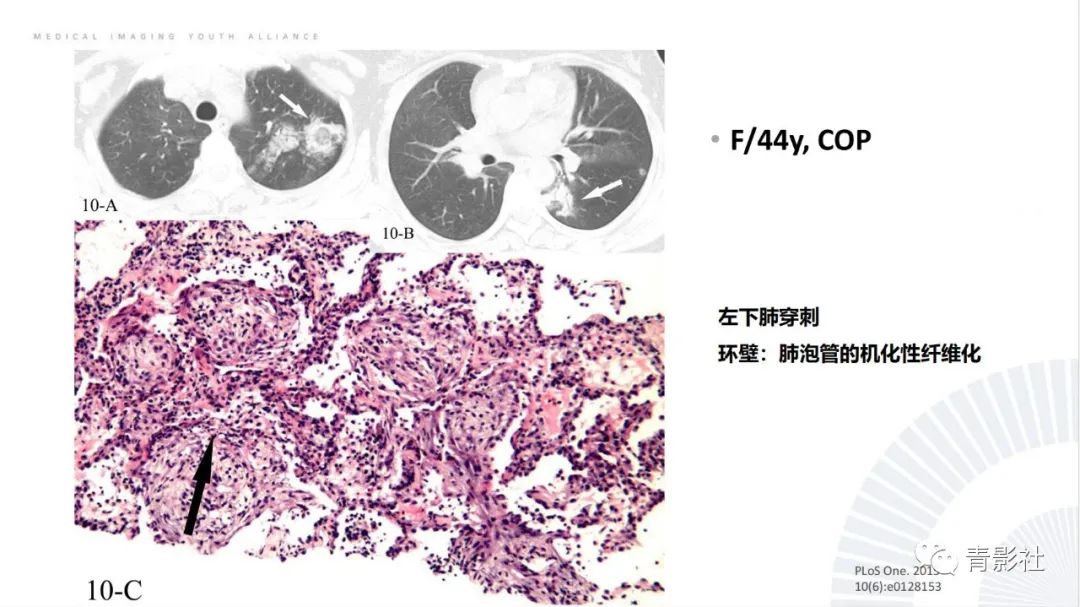

【PPT】肺部反晕征影像诊断思维-8